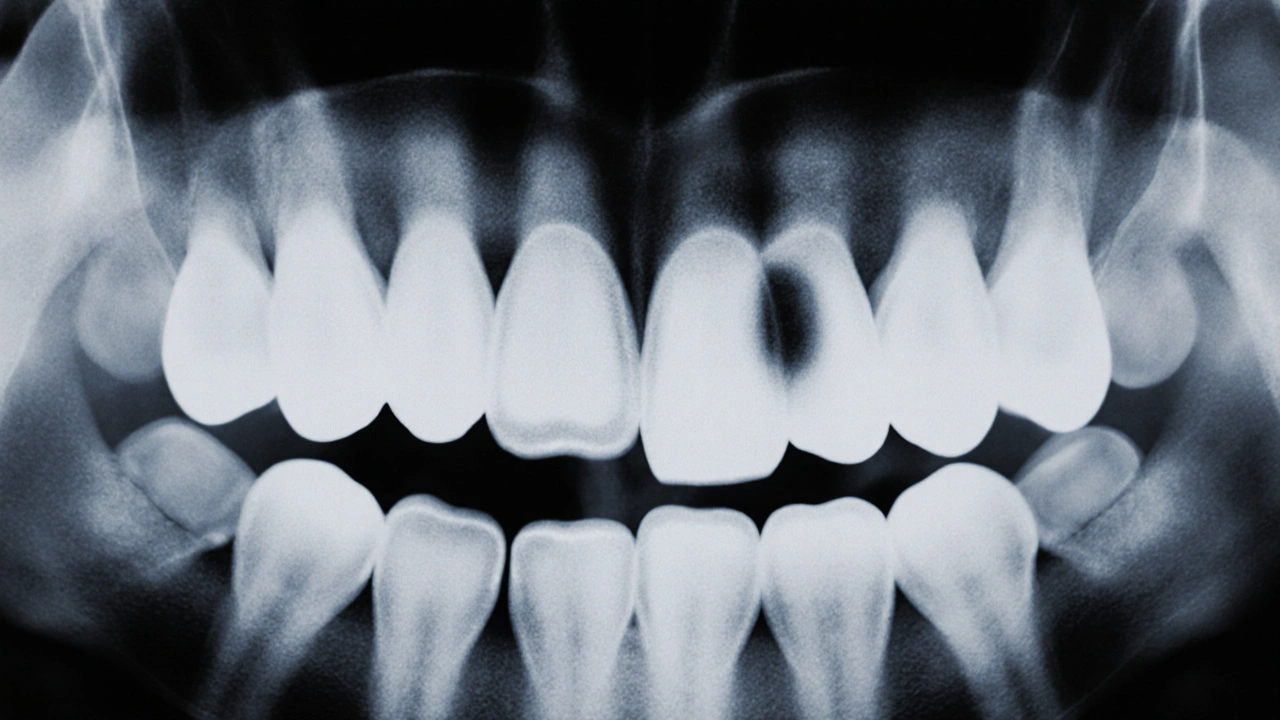

Na rentgenu se káze neukáže jako černá díra, jak si mnozí představují. Je to jemný, skoro neviditelný stín, který se skrývá mezi zuby. A právě proto je rentgen tak důležitý - bez něj byste o mezizubním kazu nevěděli, dokud by nezačal bolet. A když bolí, je už pozdě.

Co vlastně na rentgenu vidíte?

Když se podíváte na zubní rentgen, vidíte různé odstíny šedi. Černá jsou vzduchy, bílé jsou kovy, zuby vypadají jako světlé šedi. Káze je tam, kde je kost nebo zubní sklovině trochu „vyjmutá“. Vypadá to jako malá tmavá skvrnka, často s ostrými hranami, která se táhne od povrchu zubu směrem dovnitř, mezi dva zuby.

Na panoramatickém snímku je to těžké uvidět. Na bitewingovém rentgenu - tomu, který lékař dělá při každém preventivním vyšetření - je to jasné. Ten snímek zachycuje čelist od zubu k zubu, přesně tam, kde se zuby dotýkají. Tam, kde je sklovině zdravá, je na snímku jasná a hustá. Když je tam káze, ztrácí hustotu. A to se na rentgenu projeví jako tmavší oblast.